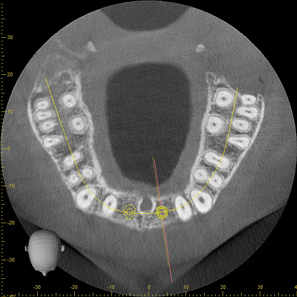

Fig 3. CBCT images show axial (Fig 2) and cross-sectional (Fig 3) views, and 3D reconstruction view (Fig 4) with virtually planned implant Nos. 8 and 9.

Figure 3

Fig 4. CBCT images show axial (Fig 2) and cross-sectional (Fig 3) views, and 3D reconstruction view (Fig 4) with virtually planned implant Nos. 8 and 9.

Figure 4